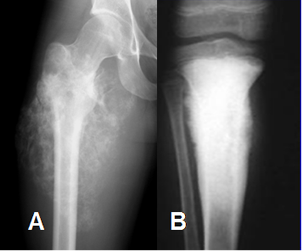

Fig 34. Matriz osteoide.

A y B: Rx AP. Calcificación osteoide de la matriz en patrón algodonoso y densa. (En marfíl).